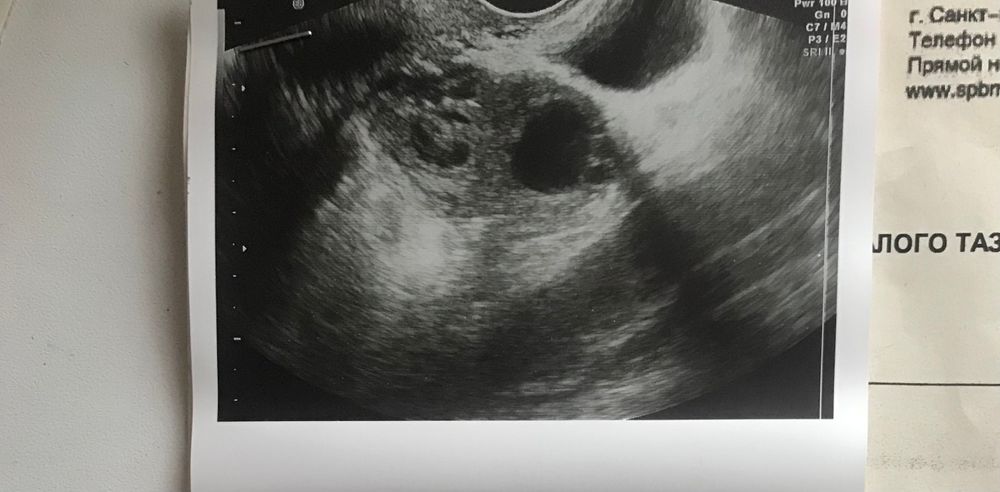

Девочки, всем привет!! Помогите, разобраться, пошла на узи по причине сильных болей в правом яичнике отдающих в ногу и поясницу. Болит уже прилично, 7 дней. Изначально думала что овуляция

В том цикле была киста слева. Врач ничего не сказала, сказала все отлично по гинекологии. Идите мол к хирургу. А киста куда делась ?? По-моему на фотографии она

киста была 4х4

На фото жёлтое тело, вероятно.

Киста жт была? Она быстро рассасывается.